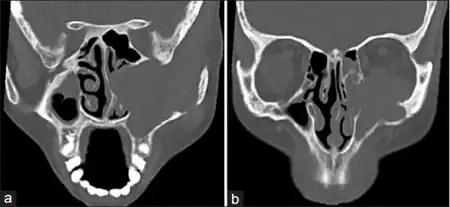

Esthesioneuroblastoma is a rare cancer of the nasal cavity. Arising from the upper nasal tract, esthesioneuroblastoma is believed to originate from sensory neuroepithelial cells, also known as neuroectodermal olfactory cells.[1]

Esthesioneuroblastoma frequently first presents as a nasal mass.[3] The most common signs and symptoms of esthesioneuroblastoma are nasal obstruction (70%) and epistaxis (50%).[4][1] Less common symptoms include hyposmia (loss of smell), headache, rhinorrhea, vision loss, proptosis, facial pain, diplopia (double vision), masses in the neck and changes in mental status.[4] Esthesioneuroblastoma occurs in the upper nasal cavity, near the optic nerves and optic chiasm. Thus, tumor growth can impinge nerve function and result in vision loss and diplopia.[5] As the tumor metastasizes to the oral cavity, there can be tooth pain and tooth mobility.[6]